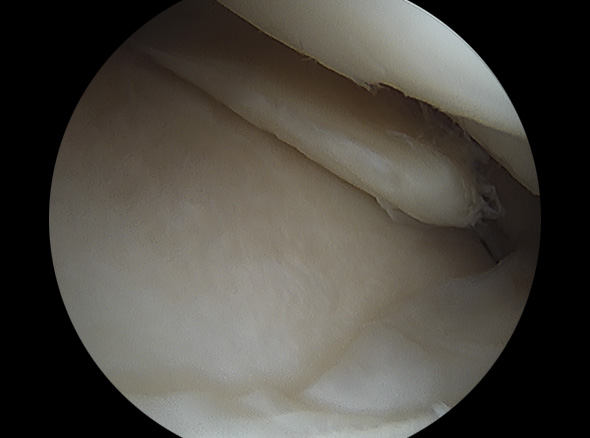

지속적인 증상이 동반된 반월상 연골판 파열에 적용하는 수술적 치료방법입니다.

불안정한 반월상연골 부위를 내시경으로 확인하여 파열된 연골판을 꿰맴

반월상 연골판 파열 정도에 따라서 절제술, 봉합술로 나눠 수술을 결정합니다.